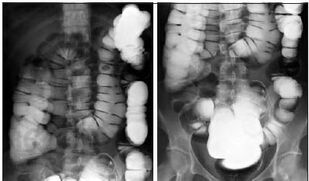

В пособии отражены наиболее часто встречаемые поражения кишечника. Освещены диагностические и прогностические критерии, тактика ведения больного с заболеваниями кишечника на всех этапах оказания медицинской помощи и основные вопросы фармакотерапии и профилактики.